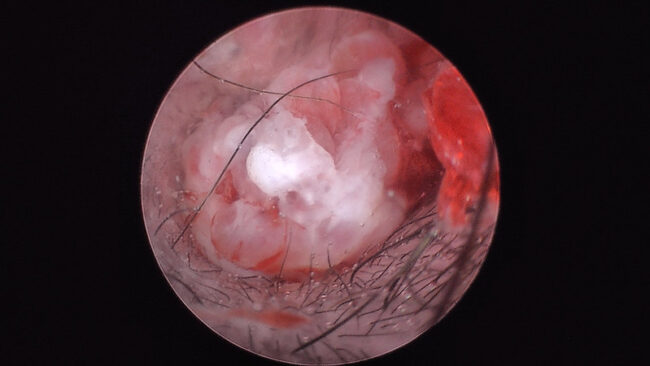

Nous évoquions dans un post précédent la propension des bouledogues français à développer des otites moyennes suppurées, comparés à d’autre races brachycéphales. Une nouvelle étude vient montrer à quel point ce risque doit être pris en considération. Il s’agit de la recension de 10 cas de méningite suppurée otogénique, c’est-à-dire issue de l’oreille moyenne/interne. Ces…